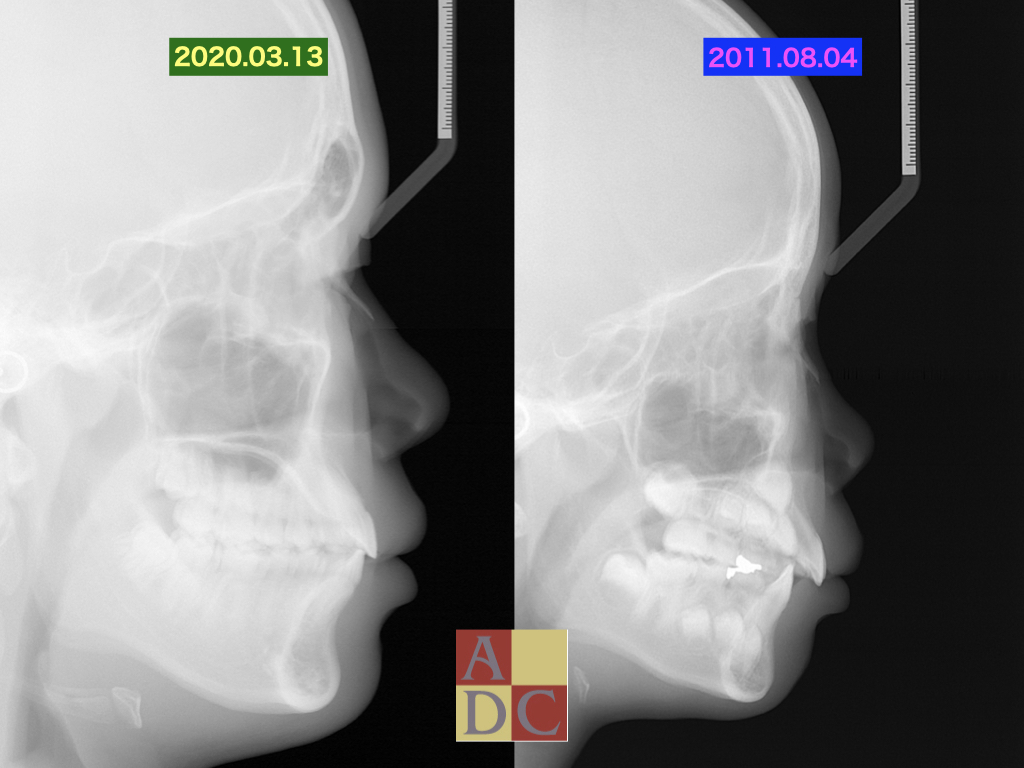

この子は紹介の子供

出っ歯だからどうにかしてほしいと、知人から・・・

放っておいたら、抜歯矯正か?外科矯正になっていたかも?

マイオブレースを使用し、非抜歯でブラケット無しで完了!!